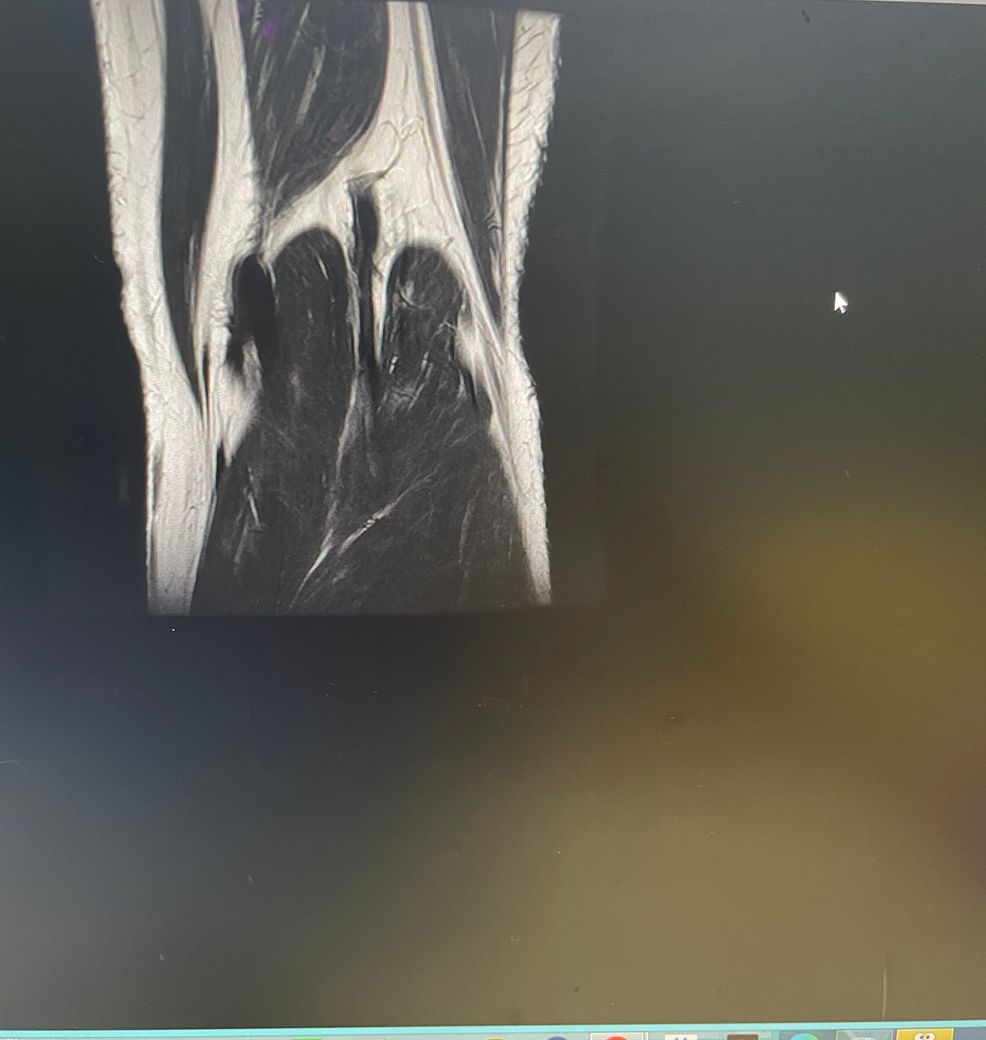

무릎 왼쪽 mri 사진 판독 부탁드리겠습니다.

십자인대에는 문제가 없지만 반월판의 문제가 있는 것으로 보입니다.

ACL 즉 전방 십자 인대에 불규칙한 소견은 있으나 Tear 즉 십자 인대가 파열되었다는

소견은 관찰되지 않는 상태이며 연골에 퇴행성 변화는 있는 것으로 보이나 이 역시 R/O

으로 확실하지 않음을 의미합니다. 결과적으로 십자 인대의 파열이 명확하지 않는 상태로

군대를 연기할 사유가 될지는 모르며 전방 십자 등 인대 손상의 경우는 명확하게 파열된

소견을 보이지 않는 경우, 군 입대에 문제가 되지는 않을 것으로 생각됩니다.